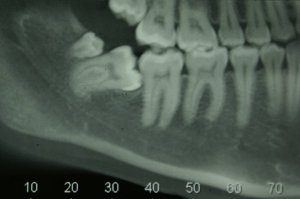

Com uma radiografia, o dentista irá definir. No entanto, quanto estiver incluso ou semi-incluso (preso ou parte dele preso), faz-se extremamente necessário a retirada. Nesses casos, o dente não nasce completamente ou somente em partes, deixando a área do fundo da boca irritada.

Em posições erradas, o dente pode ficar na diagonal, de lado, deitado ou até de cabeça para baixo, isso é causa para acúmulo de alimentos e formação de cáries, por exemplo.